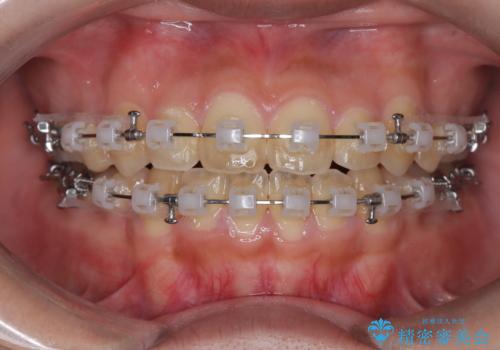

【抜歯矯正】クリア装置で1年半

- 矯正装置

- クリア装置

- 八重歯と口元が出ていることを主訴に来院されました。

レントゲンの検査において、前歯も外側に傾いてる結果であったため、上下左右の小臼歯を抜歯して配列を行いました。

歯の動きも良く短期間で治療を終えられたため患者さんにも大変満足していただきました。

クリア装置とは、当院において最も摩擦を減らした装置のため比較的動きが早く治療がスムーズに進みます。